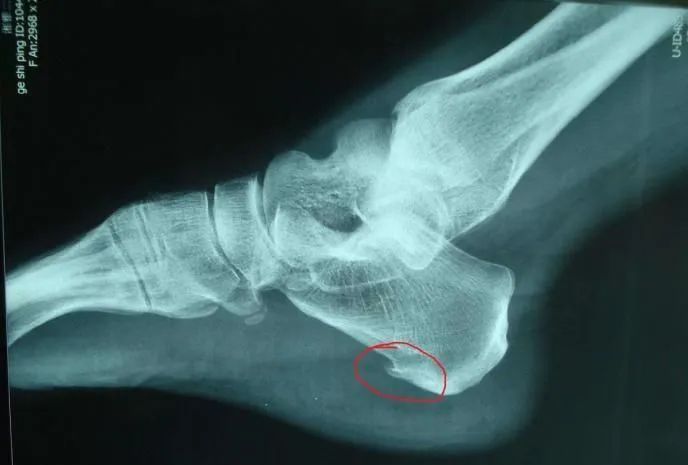

一、什么是足跟骨刺?

骨刺,是骨质增生的俗称。足跟骨刺即是足跟骨质增生,足跟骨刺是—种正常的生理退化现象,是人体的—种保护性生理反应,每个人都难以避免,区别仅仅是有的人出现得早些,有的出现得较晚些,—般在40岁以后。

五、跟骨骨刺的临床表现

足跟骨刺的症状表现与骨刺的大小、病发时间的长短、有无炎症等有关系。